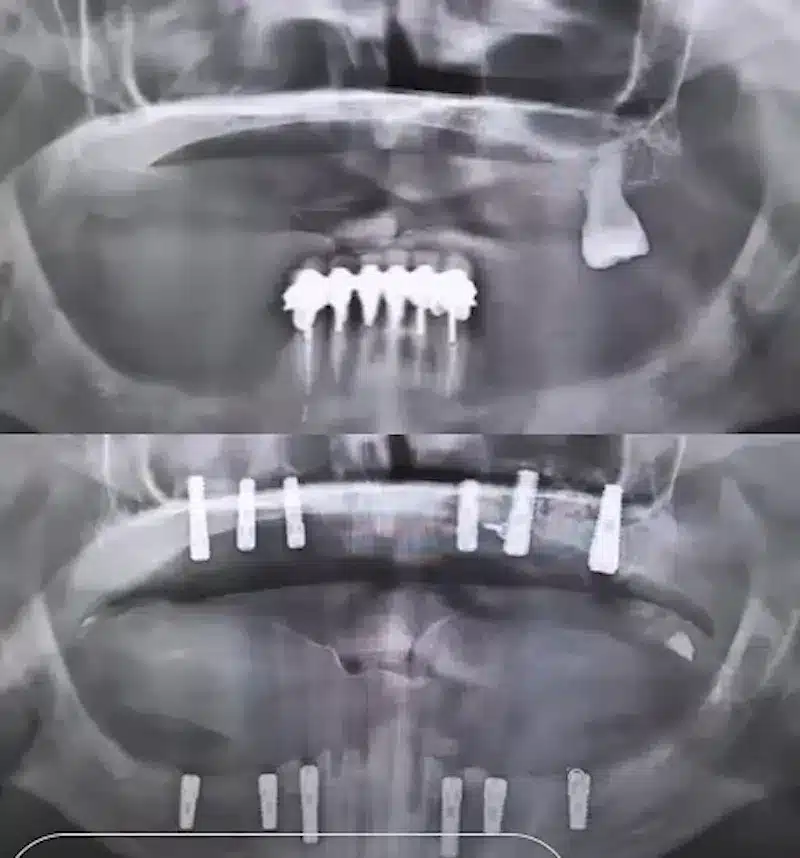

Dr. Seden Aksu is a specialist in modern implantology and surgical dentistry with extensive experience in the management of complex clinical cases. In her practice, she applies comprehensive surgical planning, minimally invasive techniques, and advanced regenerative technologies aimed at restoring both the function of the dentoalveolar system and the aesthetics of the smile. Dr. Aksu has significant experience in performing implant procedures, bone augmentation, and periodontal surgery, including the treatment of patients with severe bone loss. The primary goal of her work is to achieve stable, long-term outcomes in implant rehabilitation and the restoration of oral tissue health.